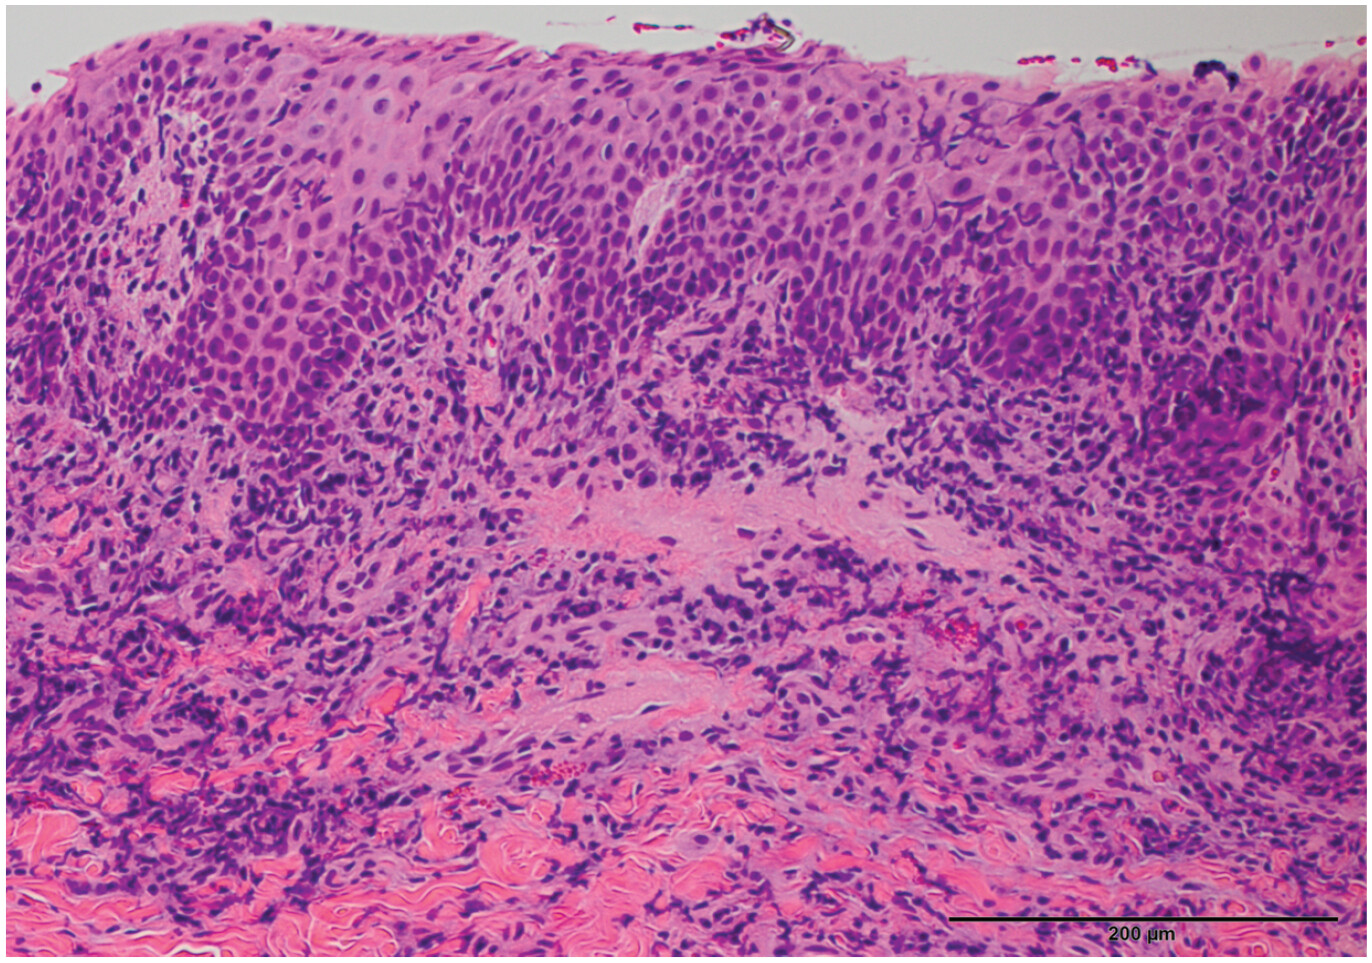

FCGS-受影响猫的黏膜上皮的典型外观是增生性的,有突出的乳头延伸至深层粘膜下(图3)。亚粘膜毛细血管通常充血,并有饱满的内皮细胞覆盖。黏膜也可能出现溃疡;在这些情况下,中性粒细胞主要分散或聚集在上皮退变区域下的基底膜/粘膜下层。已经在患有FCGS的猫的牙龈活检中记录到增多的肥大细胞。尽管它们在这种疾病中的作用尚未完全确定,但肥大细胞释放一系列促炎和免疫调节介质,即使数量很少,这些细胞也可能参与FCGS中局部炎症和免疫反应的启动、传播和持续。

图3 FCGS患者颊粘膜的组织学切片。注意到增生的上皮和突出的乳头状结构(类似手指的结构),深入到粘膜下层。20倍放大;标尺 = 20微米